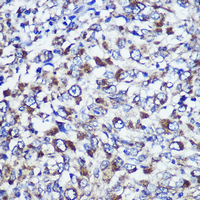

Immunohistochemical analysis of DIS3L staining in human liver cancer formalin fixed paraffin embedded tissue section. The section was pre-treated using heat mediated antigen retrieval with sodium citrate buffer (pH 6.0). The section was then incubated with the antibody at room temperature and detected using an HRP conjugated compact polymer system. DAB was used as the chromogen. The section was then counterstained with haematoxylin and mounted with DPX.